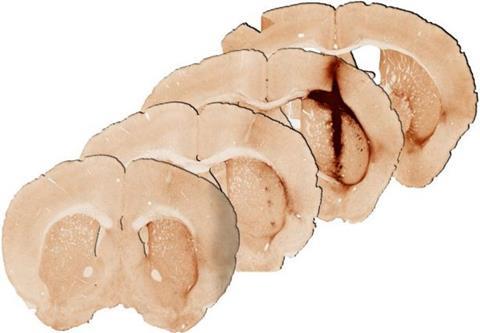

Mouse brain tissue 28 days after injection of hydrogel with myoglobin shows a higher volume of healthy grafted brain tissue, compared to injections of the hydrogel without myoglobin [Credit: Yi Wang].[/caption]

“We saw that the hydrogel incorporating myoglobin and stem cells repaired injured brain tissue. Analysis at 28 days after delivery of the hydrogel revealed significantly enhanced survival and growth of the new stem cells that are needed for healthy brain functioning, compared with a hydrogel without myoglobin,” Professor Parish said.